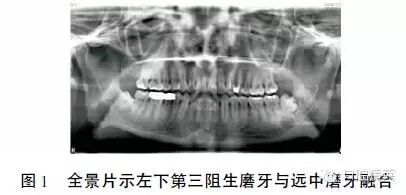

全景片显示:左下第三磨牙偏远中阻生,牙体偏大、冠根畸形,紧邻其根尖下方见一1.5 cm×1.5 cm 大小圆形囊性阴影,反应线明显,与下颌神经管重叠(1)。